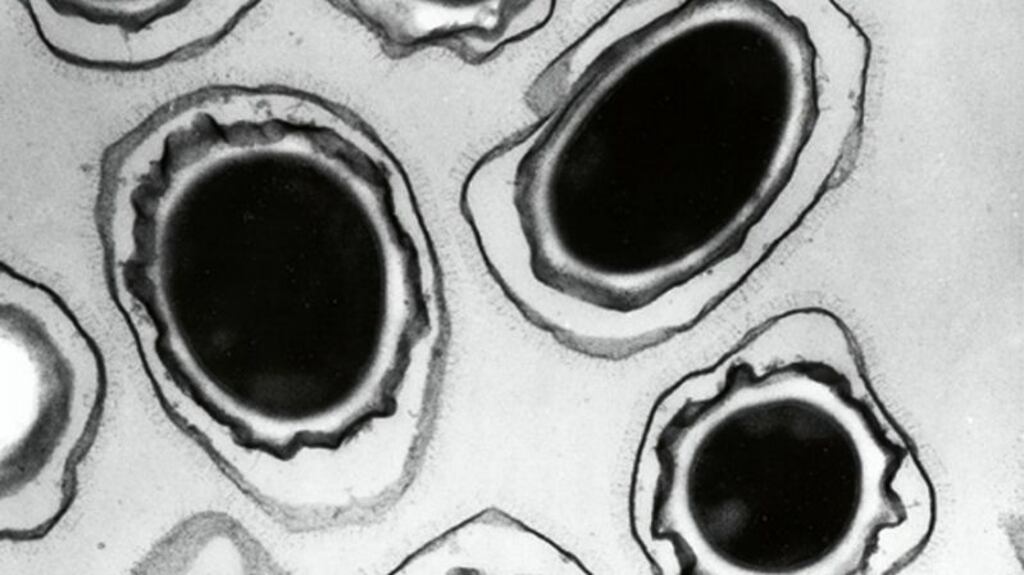

A child has died amid an outbreak of anthrax in a Siberian region where nomadic reindeer herders have been evacuated due to the epidemic, the governor said.

The appearance of the bacterial disease in the Yamalo-Nenets region is the first fatal anthrax outbreak reported in Russia in 75 years.